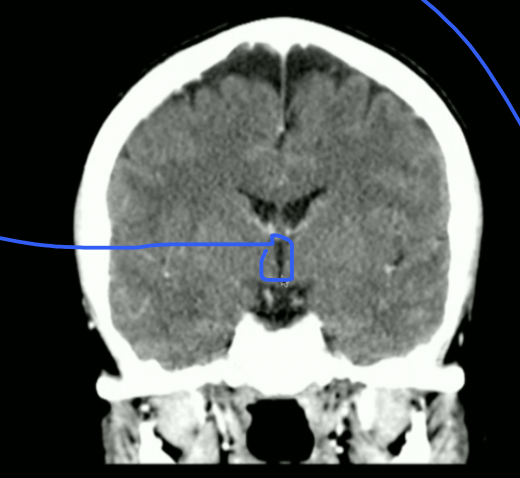

<p>What is this?</p>

What is this?

Basal Nuclei

4